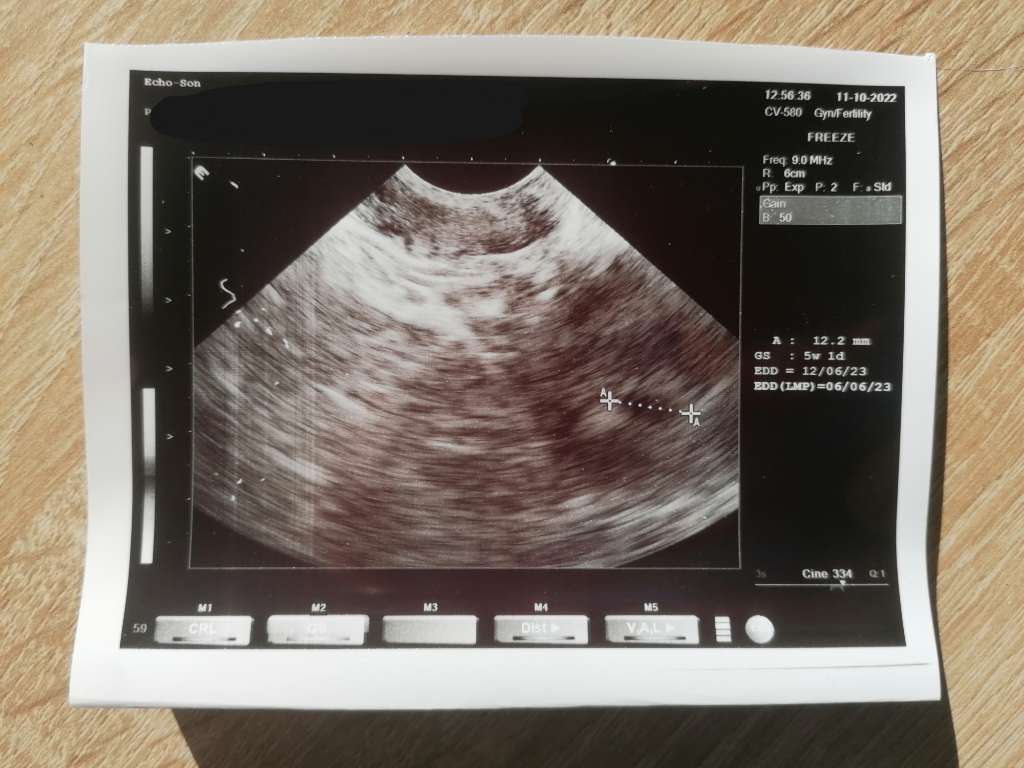

26.08. Dziś miałam wizytę i wyznaczono mi termin na 9/06/2023 ;-)Pewnie ze takpodaj datę ostatniej miesiączki